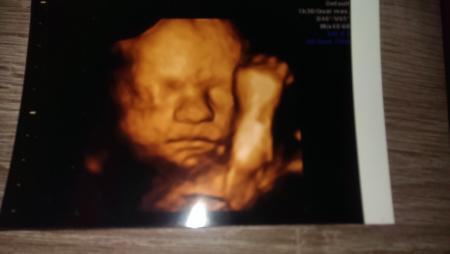

Allles zeitgerecht entwickelt die kleine wiegt schon 1580g Jetzt geht's zum ende zu

Boa was für ein tolles Bild *neid* Und stolze Maße schon:-):-):-)

Wirklich ein tolles Bild!! Sportlich, sportlich der Zwerg :)

*kreisch* ist das süüüüüüüüüüüüüüüüüüß !!!!